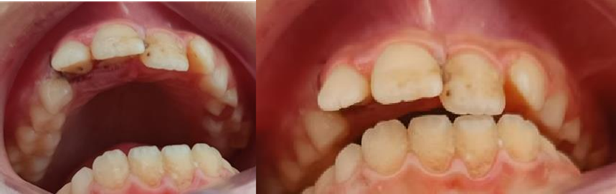

A healthy 11-years old patient referred to our department of dentistry, “Sahloul Hospital Tunisia” after two days of oral trauma. Endobuccal examination revealed a 6 mm vestibular dislocation of the 11 and 12 associated with alveolar fracture and in bloc mobility (Figure 7).

Figure 7. Endobuccal view of the patient during the 1st consultation.